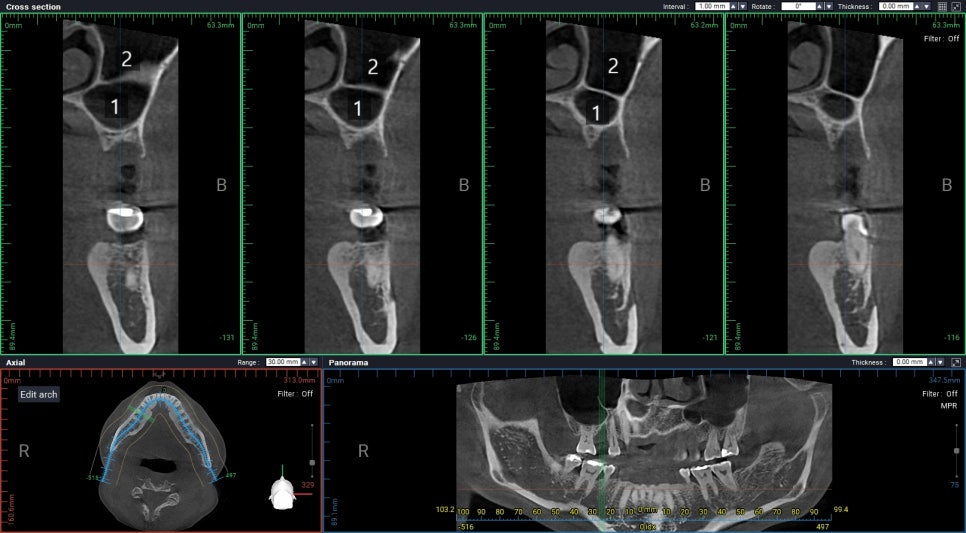

수술부위에 상악동 안에 방이 2개로 나눠져 있습니다.

발치한 지 1달이 지난 상태는

여러모로 애매한 상태입니다.

뽑은 자리가 다 아물지도 않았고

남은 뼈가 너무 없기도 하고

이 경우에는 특히 상악동 거상술이 필요한데

CT 사진에서 보시다시피 상악동 안에

방이 1개가 아니라 2개로 나뉘어져 있습니다.

이런 경우 측방상악동 거상 시 절개부위가 많아져서

환자가 많이 고통스러울 수 있습니다.

그런데 남아있는 뼈가 너무 적고

해외로 출국해야하기 때문에

수술이 실패하면 재수술할 시간적 여유도

없는 상황이었습니다.